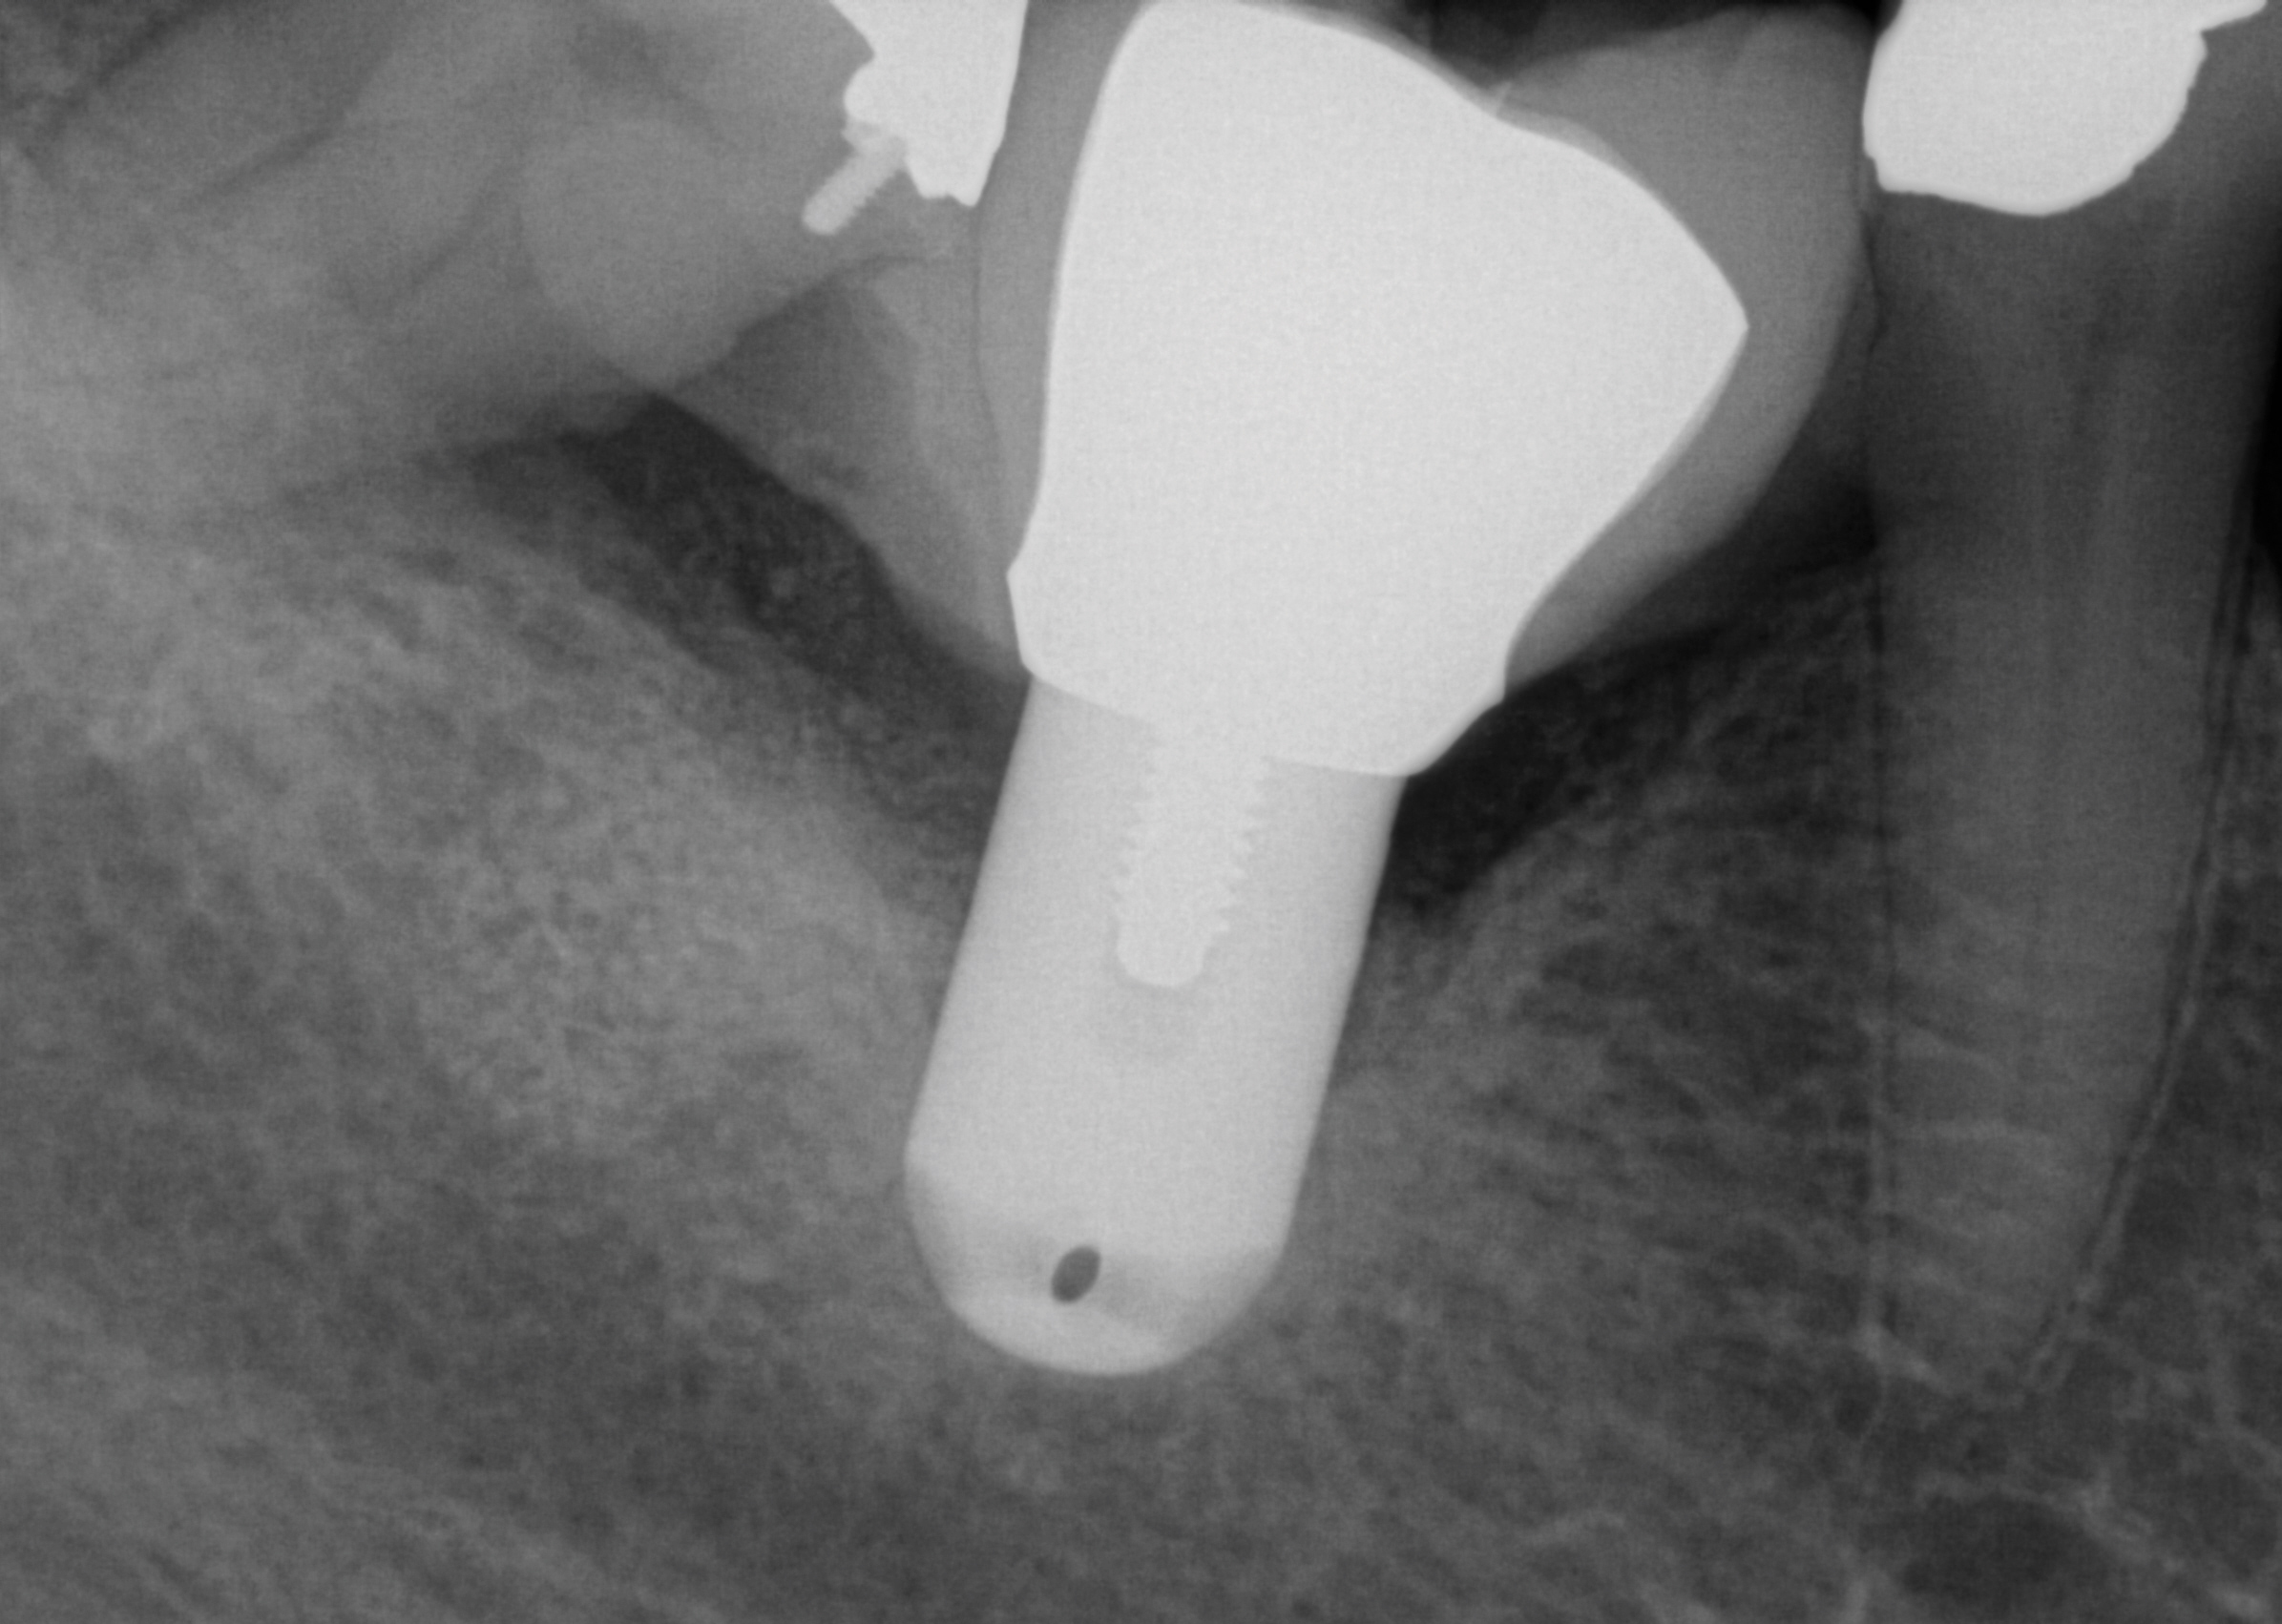

Fig 1. An implant was placed at site No. 30. Immediately after the effect of the local anesthesia subsided the patient complained of paresthesia (no pain) of the mandibular right lip and chin. A periapical radiograph taken at the time of implant placement demonstrated no apparent implant penetration into the inferior alveolar canal.

Figure 1

Fig 2. The implant restoration was completed 10 years ago and the patient has been able to accommodate the altered nerve sensation. Recently, the patient presented at one of the authors’ offices and a CBCT scan was ordered. It demonstrated that the implant at site No. 30 is closer to the inferior alveolar canal than previously envisioned and may be causing compression on the nerve.

Figure 2